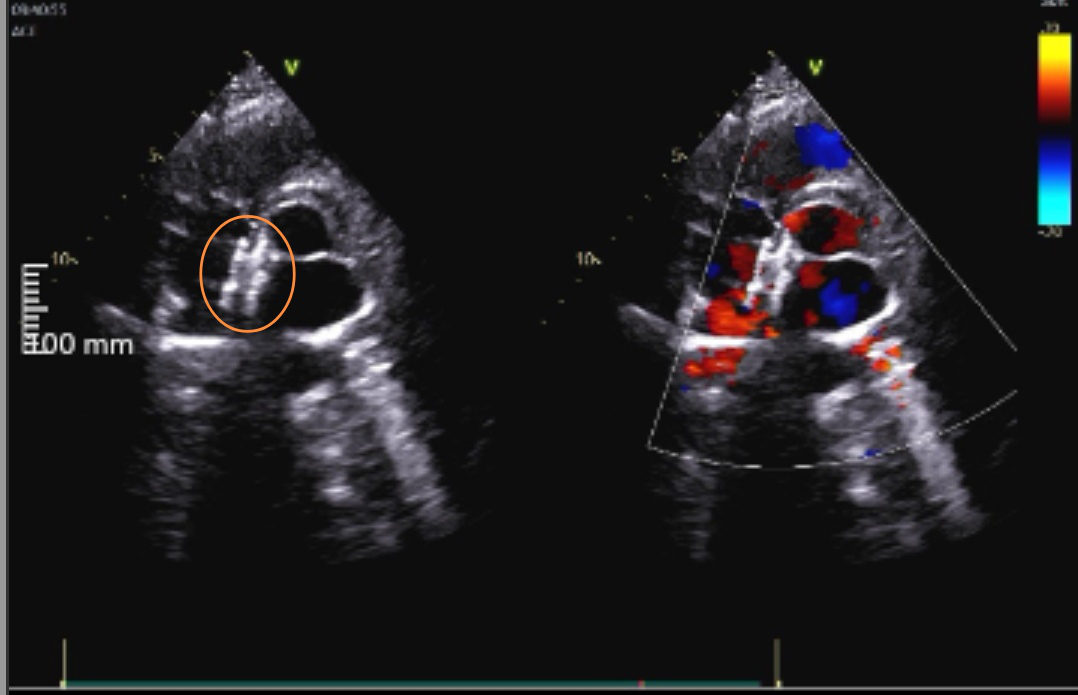

3 月 4 日,常州市第二人民医院心内科团队成功开展了全国首批、常州首台生物可降解卵圆孔未闭(PFO)封堵器植入手术,即在超声引导下采用新型生物可降解材料闭合卵圆孔的同时实现「植入无残留」。手术的成功标志着该院结构性心脏病介入治疗技术发展迈入了新的阶段。

「传统的卵圆孔未闭封堵手术多在放射成像指导下进行,并且传统封堵器是镍钛合金等材料制成,会终身存在于患者心脏内,可能有心内组织磨蚀、血栓、金属过敏、房性心律失常等并发症风险。随着技术的创新与生物材料的发展,手术可以在纯超声引导下开展,更令人欣喜的是,新型生物可降解卵圆孔未闭封堵器采用生物医用高分子材料制成,植入人体后介导自体组织再生修复,填充缺损,进而实现卵圆孔自然闭合,其主体结构约一年左右降解成二氧化碳和水排出体外。」纪元说道。

最终,在心腔内超声及透视引导下,杨女士的封堵手术过程顺利,一枚紫色的可降解封堵器成功植入她的卵圆孔未闭处。